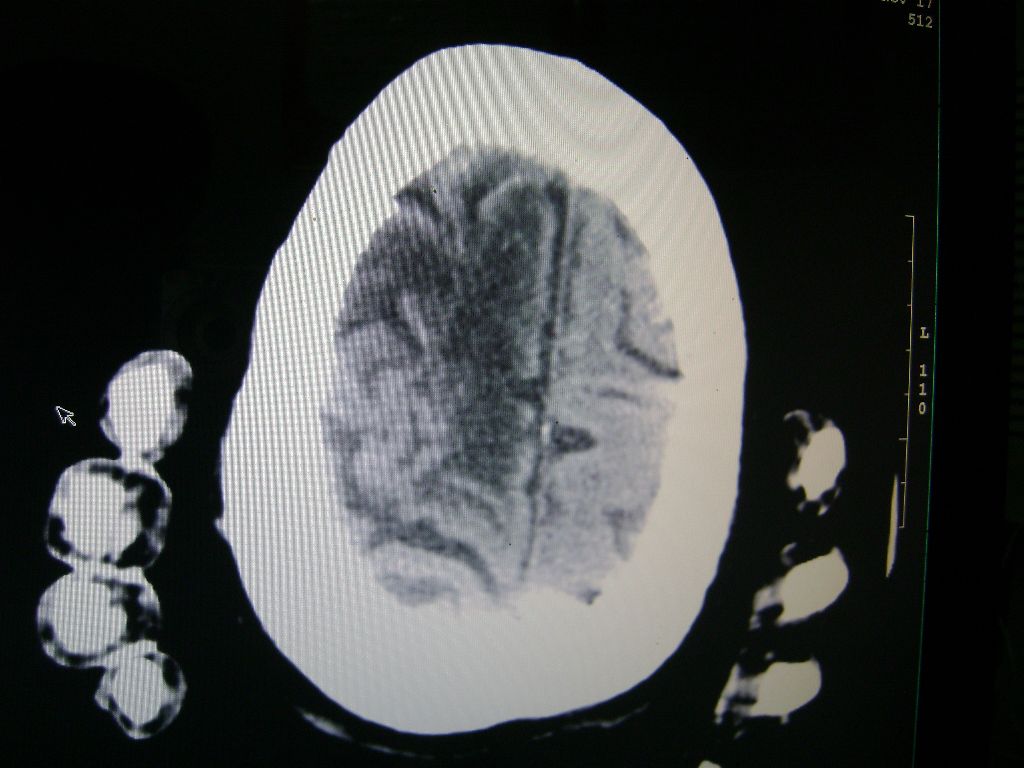

f 77 昏迷不醒

右侧额颞枕顶叶脑软化灶,脑萎缩,大脑中动脉壁钙化。

右侧额颞枕顶叶脑软化灶,脑萎缩,大脑中动脉壁钙化。不支持出血(密度高,边界清且局限)顶枕区似有新发梗塞,建议核磁

1)右侧额颞枕顶叶脑软化灶;其内高密度影,多为钙化灶。2)脑萎缩。3)大脑中动脉钙化。

右侧陈旧脑梗塞伴脑萎缩。脑内点状钙化。大脑中动脉壁钙化灶。无出血灶。

1)右侧额颞枕顶叶脑软化灶并钙化灶可能。2)脑萎缩。3)大脑中动脉钙化。 -